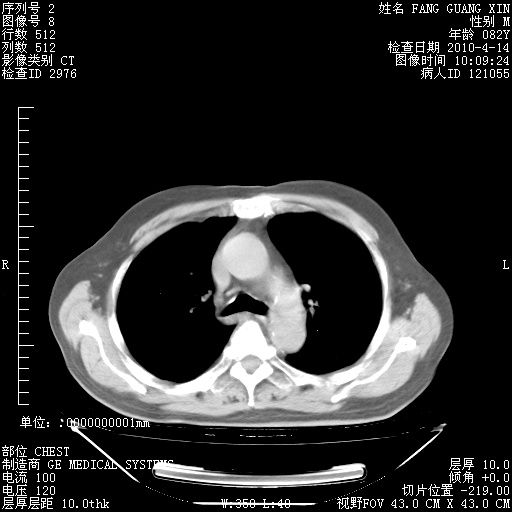

肺部CT平扫未见异常。

4月14日肺部CT